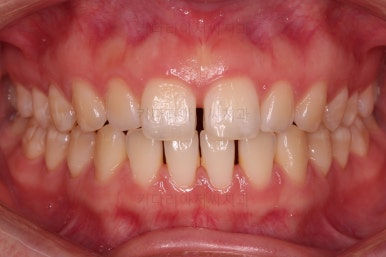

위 사진은 부산치아교정치과에 내원하셨을 대 당시의 입안 모습입니다.

치아들 사이에 전반적으로 틈이 많이 있는 상태입니다.